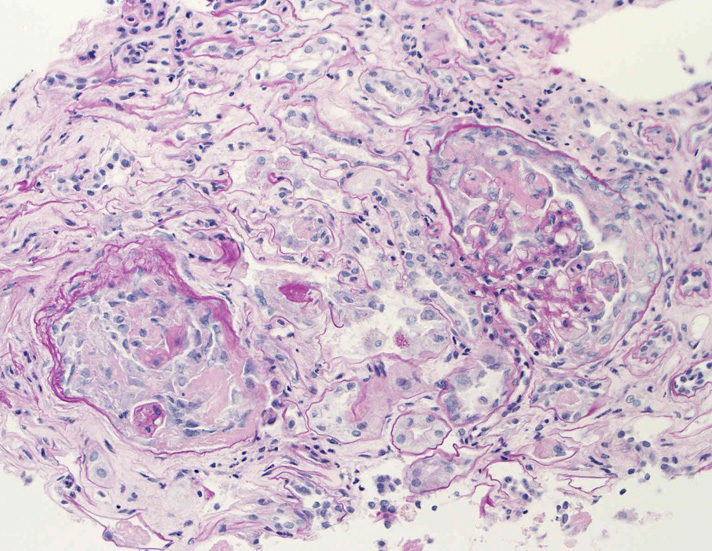

腎臓の病理組織所見-->壊死性糸球体腎炎

kidney01.jpg

kidney02.jpg

kidney03.jpg

Fig.01Fig.02Fig.03

kidney04pas.jpg

kidney05.jpg

kidney06.jpg

Fig.03(PAS)Fig.04(PAM染色)Fig.05(PAM染色)

kidney07.jpg

kidney08.jpg

Fig.06Fig.07 尿細管壊死